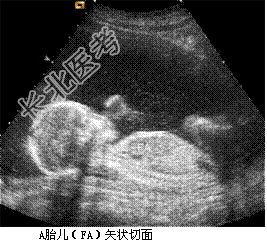

- [材料题] 孕妇,30岁,孕2产0孕22周。超声(孕12周):宫内妊娠,单绒毛膜囊双羊膜囊双活胎,A胎儿NT0.32cm,B胎儿NT0.12cm。孕22周复查超声如下图。

- 简答题1、根据上述声像图,试描述。